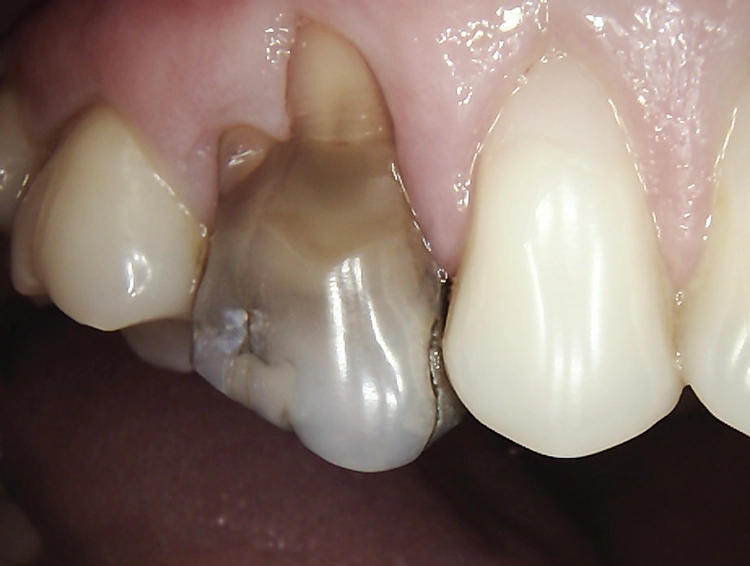

Abb. 2: Repräsentativer Fall von ABH Grad B Septus Typ II. a) Ansichten vor der Installation. Röntgenaufnahme der periapikalen Läsion an einem wurzelkanalbehandelten Molaren und klinische Ansicht der Typ-II-Socket nach der Extraktion. b) Die Ansichten nach der Installation zeigen das Implantat innerhalb des interradikulären Septums und das über dem Implantat platzierte A-PRF. c) Nachuntersuchungen nach 10 Tagen bzw. 2,1 Monaten. Die Röntgenaufnahme zeigt die Knochenbildung zwischen der Sinusmembran und dem apikalen Teil des Implantats. d) Jüngste Nachuntersuchung nach Einsetzen der Prothese.